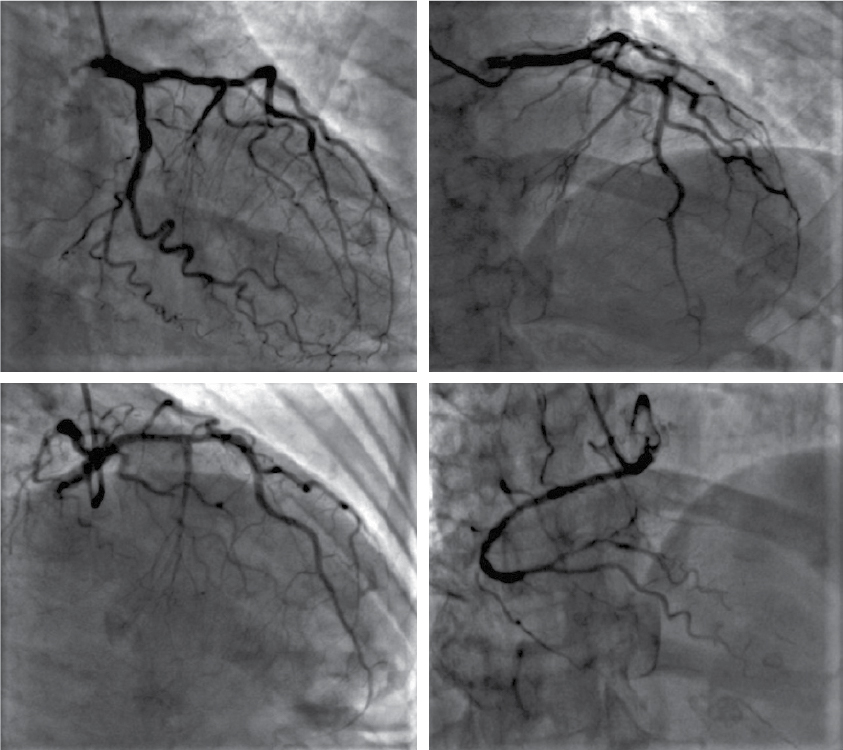

A 75-year-old diabetic female presented to the emergency department with complaints of acute onset shortness of breath and chest heaviness. She did not complain of any other abdominal or chest symptoms. Other than emotional frailty owing to social loneliness, her personal and family history were unremarkable. She was living with normal coronaries evaluated 4-year back for chest pain with ST-segment elevation on electrocardiogram (ECG). Follow-up ECG (Fig. 1A) and transthoracic echocardiography (TTE) over last few years were unremarkable. On general physical examination, patient was seen to be anxious. The heart rhythm was regular with a rate of 108 beats/min; the blood pressure was 130/80 mmHg and respiration was thoraco-abdominal with a rate of 24 breaths/min. Findings from review of the systems, other than as reported above were normal. A 12-lead surface ECG showed sinus tachycardia and ST-segment coving with T-wave inversion in precordial and limb leads (Fig. 1B). Qualitative cardiac troponin T was negative and routine biochemical analysis including complete blood count, renal and liver function tests were unremarkable. TTE revealed severe left ventricular systolic dysfunction (ejection fraction about 35% by Simpson) with marked regional wall motion abnormalities in the mid anterior, mid-septal, mid inferior and apical segments of the left ventricle (Fig. 2A and 2B). The patient was immediately shifted to the catheterization laboratory, where coronary angiography was done. Angiography revealed normal coronary arteries with mild plaquing of major epicardial vessels (Fig. 3).

Figure 3. Coronary angiogram demonstrating normal epicardial coronary arteries.